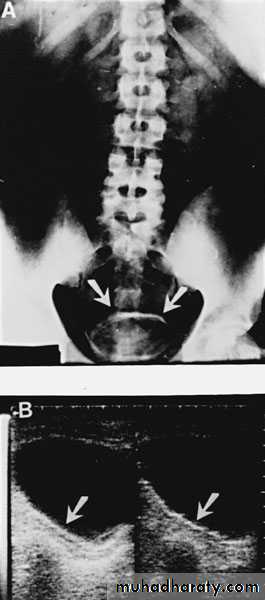

U/S: hydronephrosisIVU: diagnostic , hydronephrosis with fixed stenotic segment or complete obstruction

CT scan: hydronephrosis that ends abruptly

The ‘adder head’ on excretory urography

is typical.

Cobra (Adder) head appearance of ureterocele